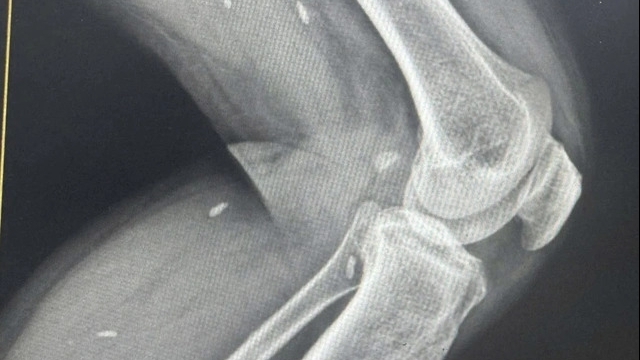

Giám đốc Sở Y tế Hà Nội nhấn mạnh, thành phố tiếp tục triển khai mở rộng mô hình “Bệnh viện chị - em” nhằm tăng cường hỗ trợ chuyên môn giữa các bệnh viện tuyến trên và tuyến y tế cơ sở dựa trên ứng dụng công nghệ thông tin. Đồng thời, đẩy mạnh ứng dụng công nghệ thông tin trong việc đặt lịch khám; tư vấn, chăm sóc sức khỏe người bệnh tại các cơ sở y tế; sử dụng công nghệ trí tuệ nhân tạo hỗ trợ công tác khám chữa bệnh, vật lý trị liệu, điều trị tâm lý, phẫu thuật... giúp người dân dễ dàng tiếp cận với các dịch vụ y tế ngay tại cơ sở.